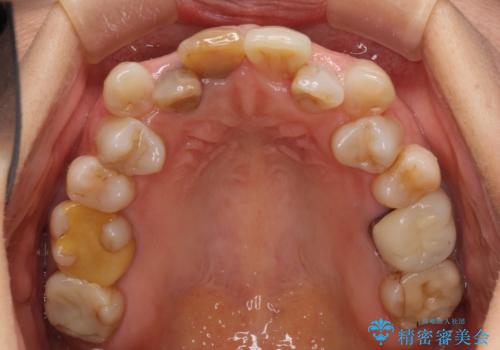

変色した前歯のオールセラミック治療

- 前歯の変色が気になるとのことで来院された患者様です。

歯並びに問題があるため、矯正治療の提案をしましたが、変色の改善のみ(オールセラミッククラウンによる審美補綴治療のみ)とすることにしました。

矯正治療を行う必要性は理解いただきましたが、「今さら歯並びを整えても・・・」という思いが強かったようで、何度もカウンセリングを行った結果、審美補綴治療のみとなりました。